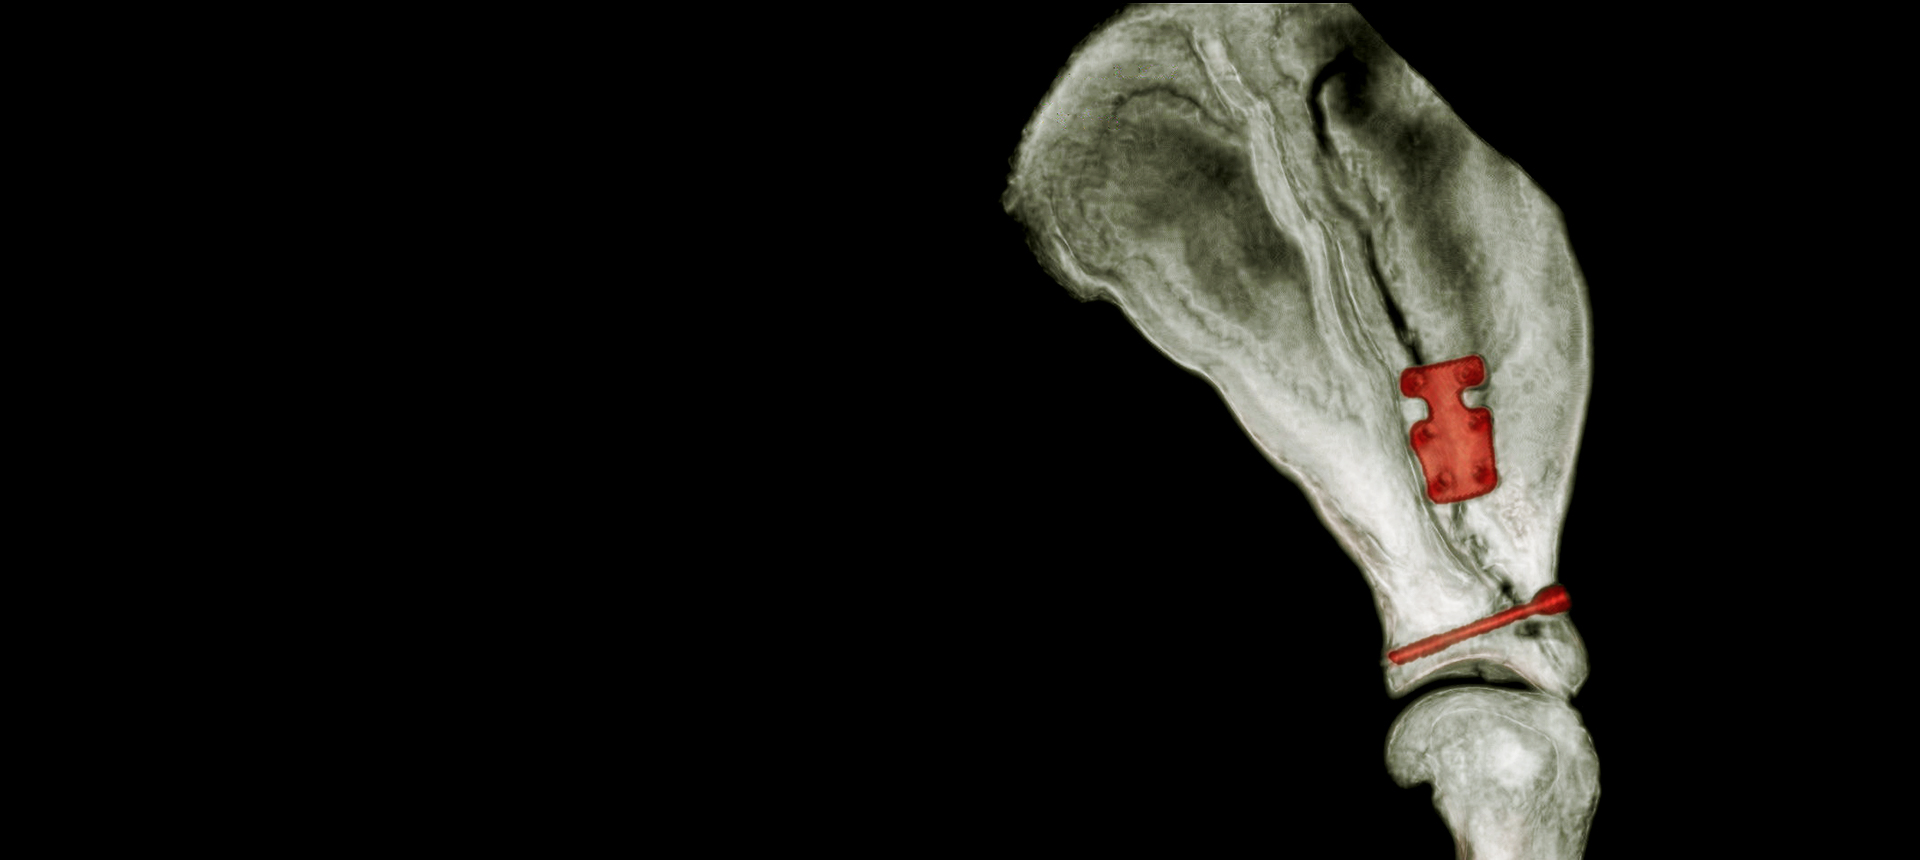

Case Overview In November 2025, Skeeter, a 14-week-old Doodle puppy weighing ...

Products